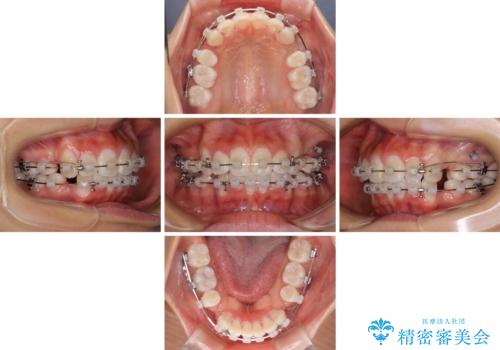

口元の突出感を改善 2年弱での抜歯矯正

- クリアブラケット

- 1年7ヶ月

- 出っ歯とデコボコを気にして来院された患者様です。

口元の突出感を改善するため、上下左右第一小臼歯4本の抜歯を行い、ワイヤー装置による矯正治療を行うこととしました。